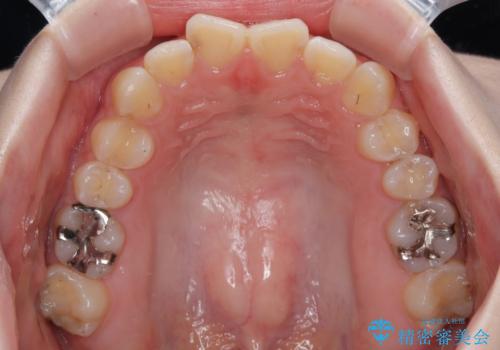

- 上下前歯部のデコボコを気にして来院された患者様です。

叢生は軽度であったため、マウスピースでもワイヤー装置でも対応可能でしたが、マウスピースを長時間使用する自信がないとのことでワイヤー装置にて矯正治療を行うこととしました。